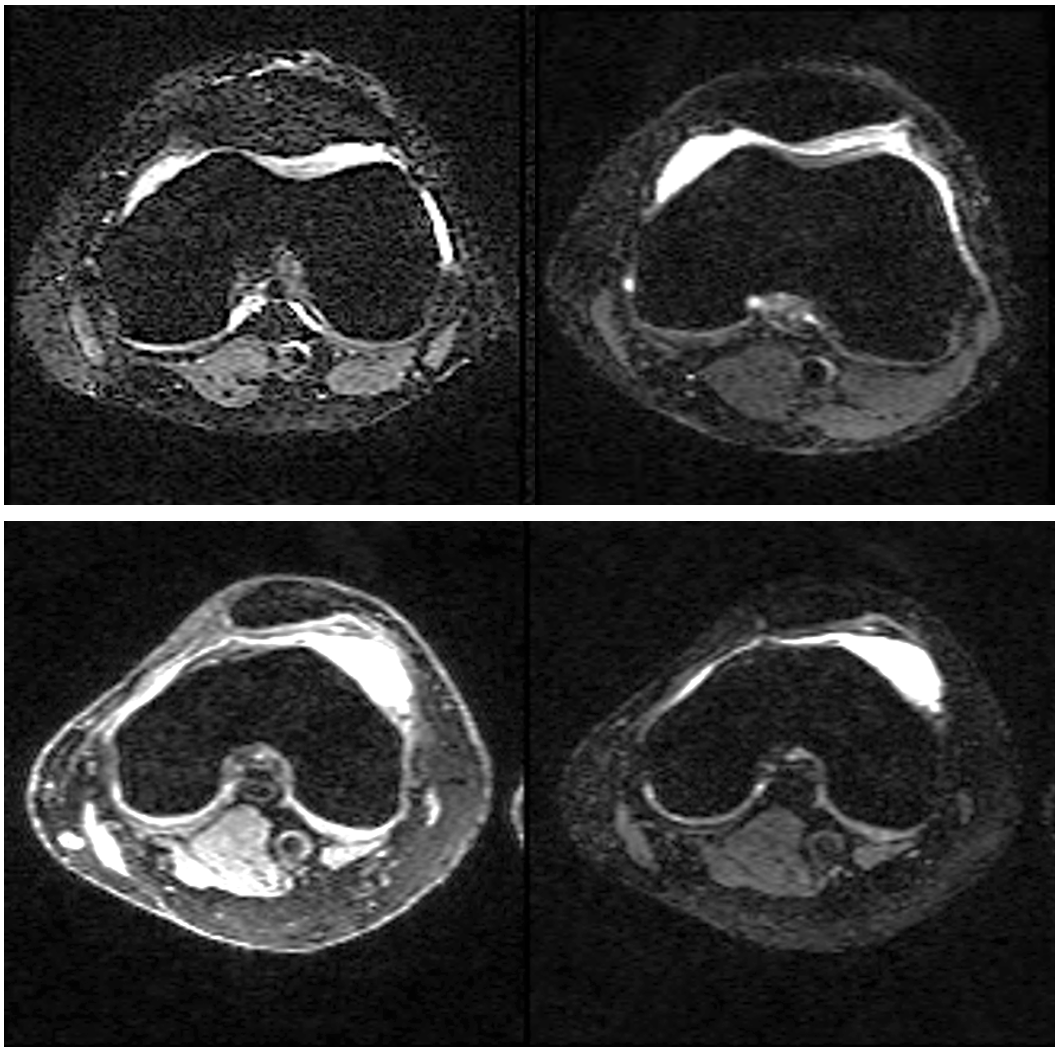

For proof-of-principle, we used the publicly available SKM-TEA dataset [37] which contains paired images from double-echo in steady state (DESS) gradient echo knee exams consisting of 3D multi-coil k-space data collected at two different echo times as well as reference complex-valued reconstructions based on parallel imaging. An example of paired images is show in Fig. 3, noting the weaker intensity of the second echo due to signal relaxation. Training data pairs (x1,x2)subscript𝑥1subscript𝑥2(x_{1},x_{2}) were normalized jointly by the 99thsuperscript99th99^{\mathrm{th}} percentile value of the reference magnitude image for x1subscript𝑥1x_{1}. We trained two different score models, sθ(x2)subscript𝑠𝜃subscript𝑥2s_{\theta}(x_{2}) and sθ(x1,x2)subscript𝑠𝜃subscript𝑥1subscript𝑥2s_{\theta}(x_{1},x_{2}), which model the marginal and joint score functions respectively. The input sizes to the marginal and joint score networks were 222 and 444 channels to account for real and imaginary components of one or two images respectively. We used 100100100 slices from 150150150 different volumes (15,0001500015,000 slices in total) to train the networks. The networks were trained for 80,0008000080,000 steps with a batch size of 444. Representative random samples taken via the annealed Langevin dynamics update equations (Eq. 7) [19] are shown for both the marginal and joint score models in Fig. 4.

Refer to caption

Figure 3: Example of an image pair in the publicly available dataset used for training and testing [37]. (Left) x1subscript𝑥1x_{1}, (Right) x2subscript𝑥2x_{2}. The dynamic range for both subfigures is the same.